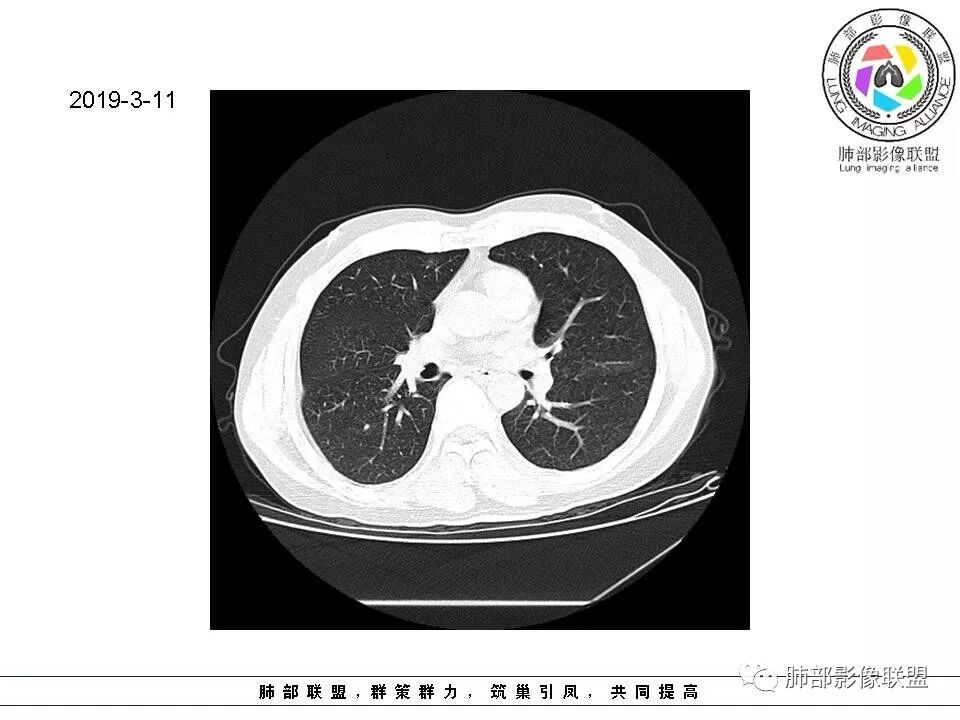

群内讨论

杨泽锋:很难通过一次CT检查来判断小结节的性质炎性结节可能大理由:病灶很小但是很密实毛刺比较长百事可乐:右肺中叶内侧段实性小结节,毛刺、分叶,胸膜牵拉。考虑MIA。李:实性结节,形态不规则,考虑炎性肉芽肿紫气东来:右肺中叶实性结节,毛刺分叶,考虑恶性。穿越七海的风:右肺上叶近胸膜下小结节,实性度较高,肺内淋巴结吧,可随访观察张帅:晨读,右肺上叶前段小结节病变,病灶内可见细支气管穿过,局部血管略增粗,病灶边界清,可见软毛刺,3月胸CT较2月貌似密度减低,毛刺变小,考虑良性病变,炎性病变?春秋:患者51男性,右上叶前段结节,形态不规整,明显分叶,前后变化不明显,考虑恶性!Yiren  Sishui(厶水伊人):小结节,密度较实,有多条线状影,胸膜下分布,肺内淋巴结?炎性肉芽肿?建议随访。东哥:晨读:右肺上叶小结节,不规则,可见分叶,整体收缩,两次CT变化不明显,先考虑良性可能我心飞翔:右上肺实性结节,长毛刺,考虑良性病变王秀仙:晨读:右肺上叶结节,边缘毛刺,一个月后,病灶略有增大,边缘小叶间隔阻挡,考虑腺癌。Shelia🌞:晨读,右肺上叶前段胸膜下小结节,形态不规则,以平直收缩为主,可见u型凹陷,长毛刺,1月复查感觉变化不大,考虑炎性病变,建议继续随访复查除外腺癌一切∮随缘:晨读病例:     右肺上叶前段可见一不规则结节,边缘可见分叶,毛刺,清晰的GGO,近端牵拉血管树,未见明显支气管截断,中年男性,体检发现,综合考虑微浸润腺癌,待排炎性肉芽肿,建议短期随访。

Ao..葉偲雨!👑:右肺中叶内侧段小结节,边缘毛刺,部分层面平直,第二次复查有凹陷,密度似乎比之前淡泊一点(肿瘤的生长周期一个月一般不会有太多变化),大小范围基本稳定,LU-Rads 4a类,炎性结节可能,建议3个月后复查或pet

南边:51岁男性,体检发现右肺结节这个年龄段的男性,啥都可以发生,也属于肺癌的高危人群南边:首先是实性还是GGO?好像实性吧

如果实性病变,边缘收缩,可以考虑炎性, 但是边缘有边界清楚GGO,一定要警惕恶性,还有粗短毛刺更要小心撇开其它,看到这个图,除非你怀疑假象,不然就是要考虑腺癌的可能

边界清楚GGO,短毛刺,这要小心瘢痕癌可以多为腺癌复查没变化,与血供有关,属于休眠期张国祯教授的理论:腺瘤样增生、原位癌都属于偏良性,就是没有侵袭性;以后发展——侵袭可以,不变可以,部分可能还会凋亡(比较少)

结果

原位腺癌